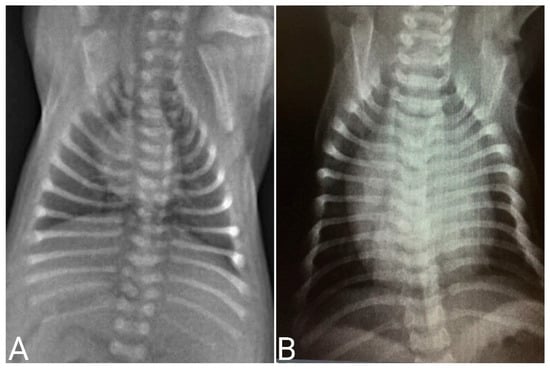

Radiographic Examination